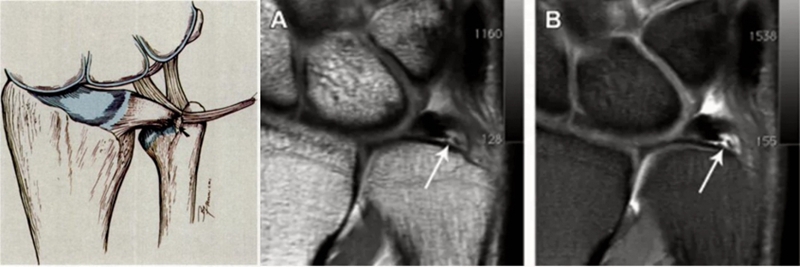

ⅠA,TFCC中心穿孔,A、B三角软骨盘正常弓形低信号缺损;C轴位显示三角软骨盘中心的高信号区与D关节镜一致

ⅠB,TFCC尺侧撕裂;TFC尺侧附着处信号增高

ⅠC,尺三角韧带撕裂

ⅠD,TFC桡侧撕裂,桡侧附着处及桡尺关节处信号增高